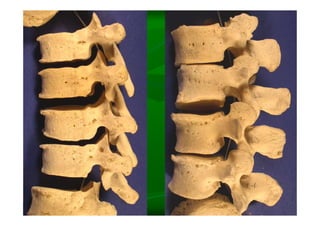

Este documento describe la columna vertebral humana. Está compuesta de 33 vértebras divididas en 7 cervicales, 12 torácicas, 5 lumbares, 5 sacras y 4 cóccigeas. Cada vértebra posee un cuerpo, pedículo, apófisis transversas, apófisis espinosa e inferior y laminas. Las curvaturas de la columna son la lordosis cervical y lumbar y la cifosis torácica y sacra.